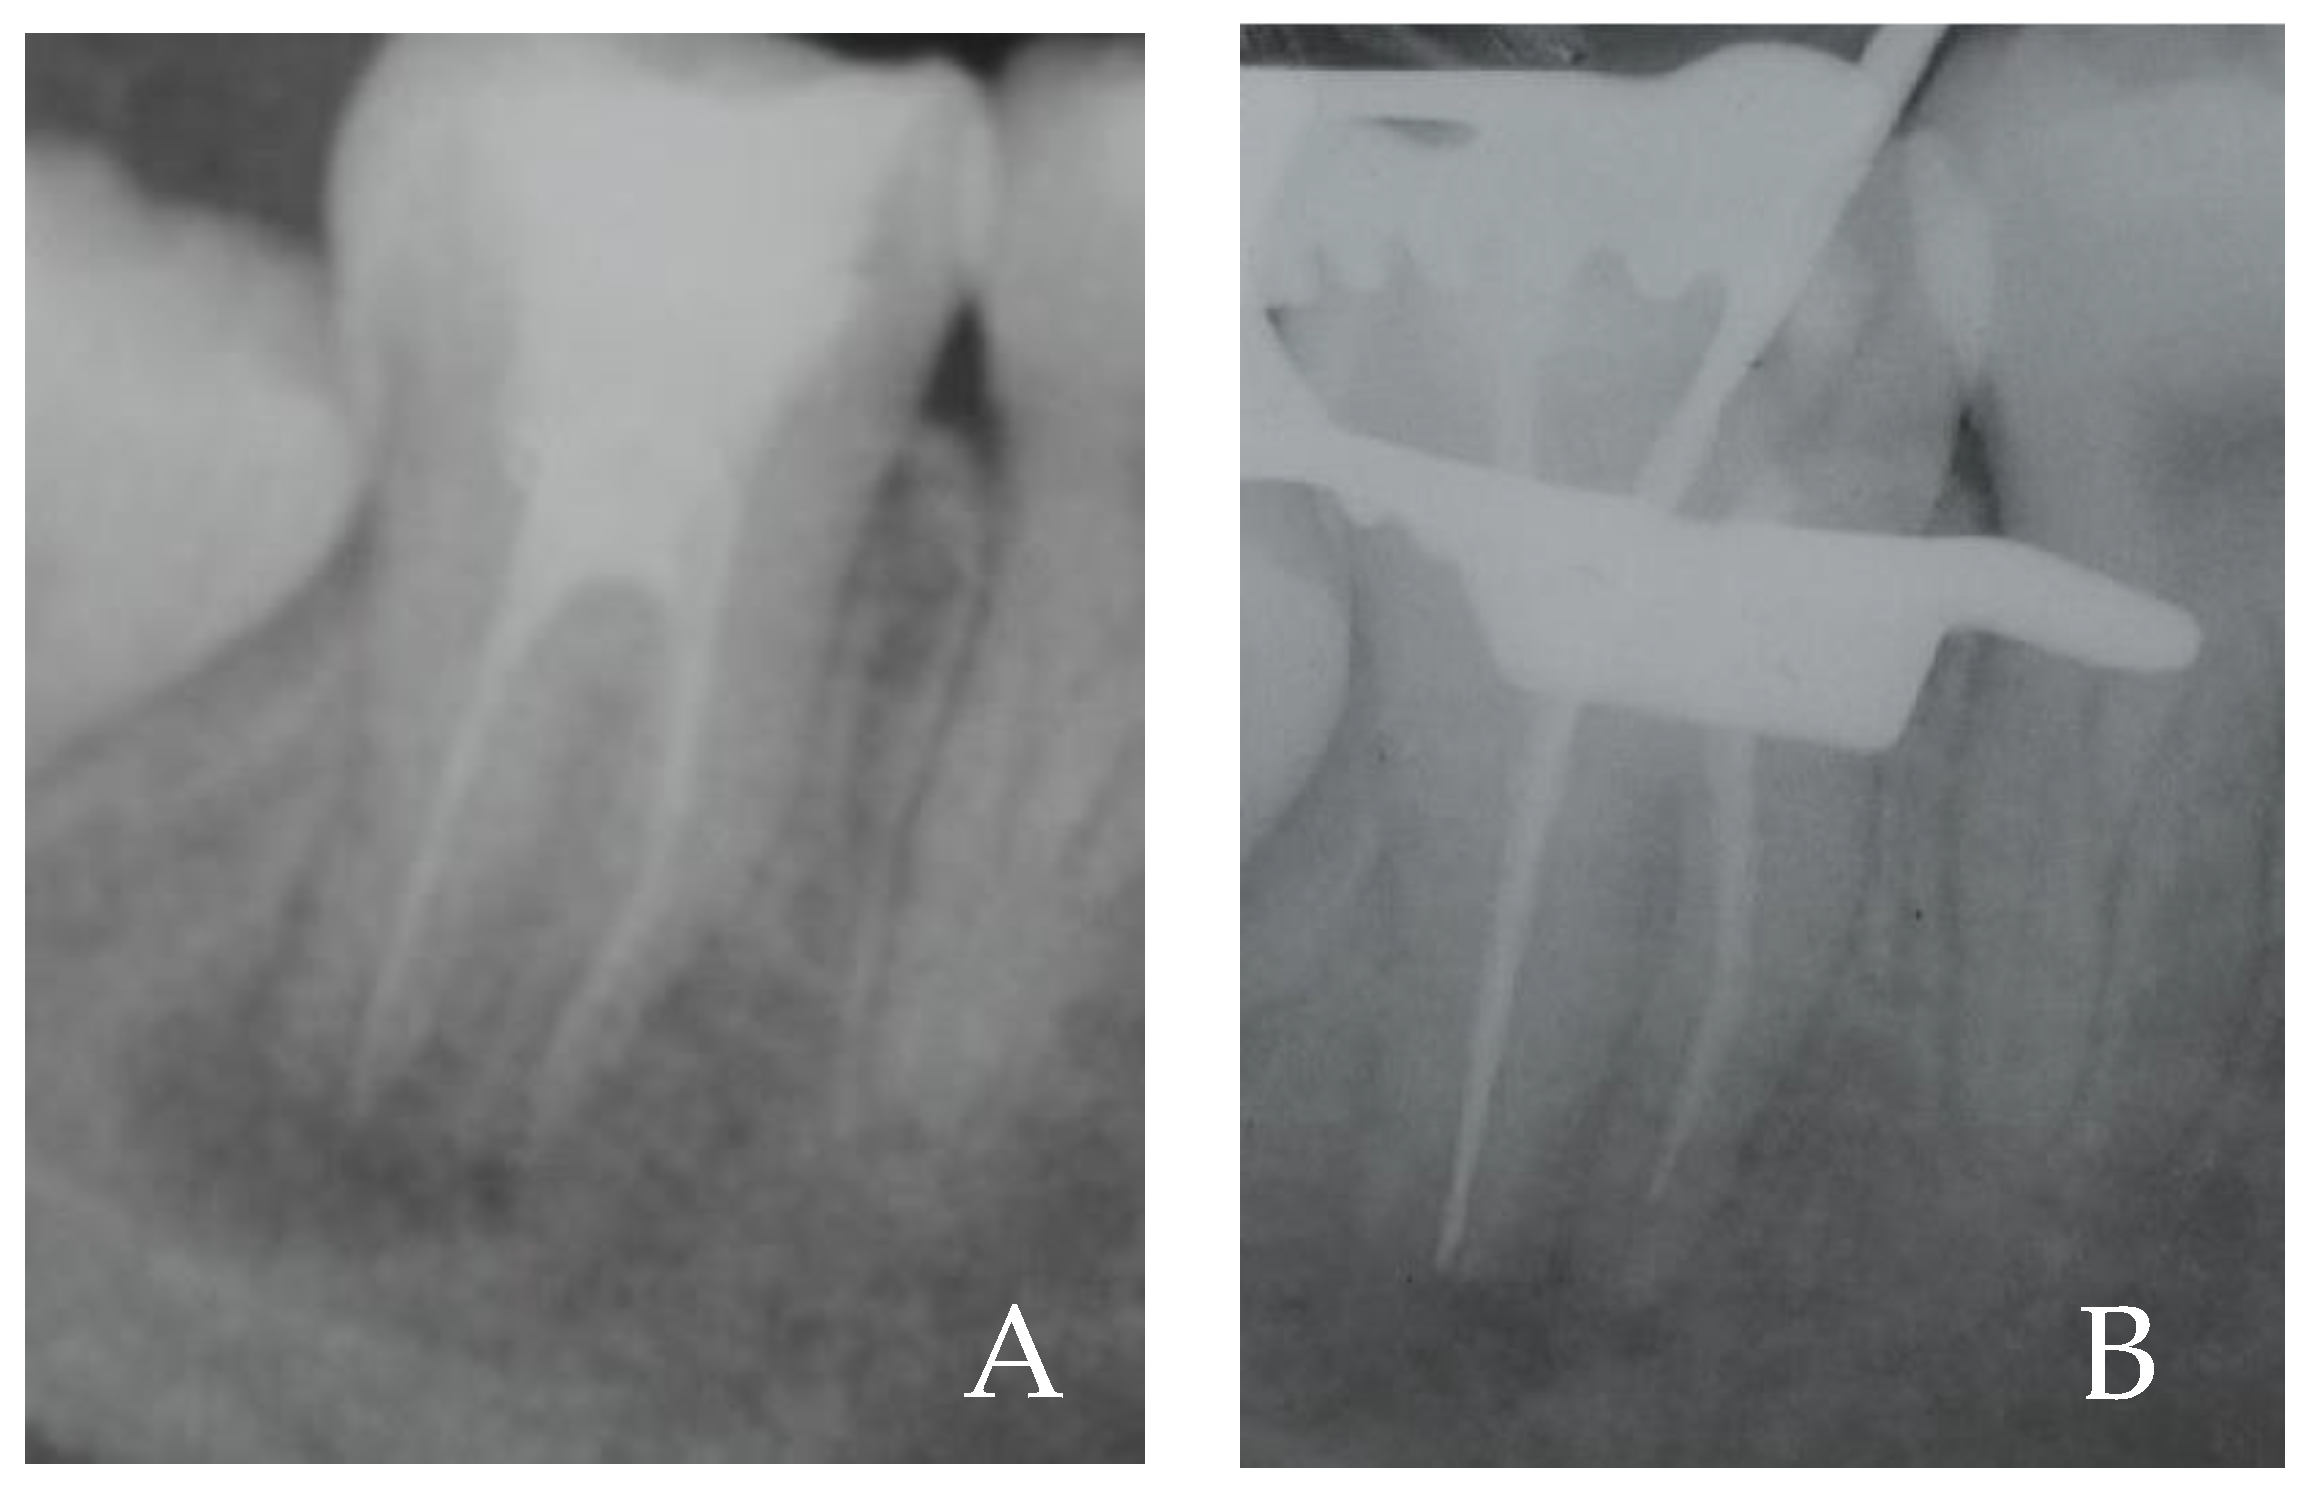

| In Vivo Test | CFU/mL |

|---|---|

| 1 sample (After working length) | 420 |

| 2 sample (After ALAD 45 min) | 210 |

| 3 sample (After ALAD/LED 7 min) | 0 |